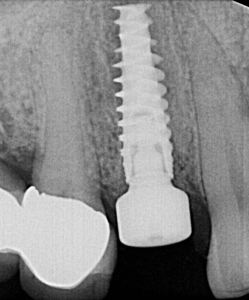

Preoperative 3D imaging is helpful in visualizing the patient’s anatomy and screening the ideal candidate. Since there is limited bone available, a dental implant with aggressive threading is important to obtain good primary stability. Typically, the socket is larger than the diameter of the dental implant and a bone graft is required to fill the space. A large stock, or customized healing abutment, can then be used to contain the bone graft and allow for ideal soft tissue healing.

Immediate implant placement in extraction sockets is a predictable procedure with favorable results. Immediate placement provides a tremendous benefit for patients as it eliminates the need for a second surgery and significantly reduces treatment time. With immediate placement patients can receive their new implant restoration four months after extraction, compared to the traditional eight month waiting period with two or more surgeries.